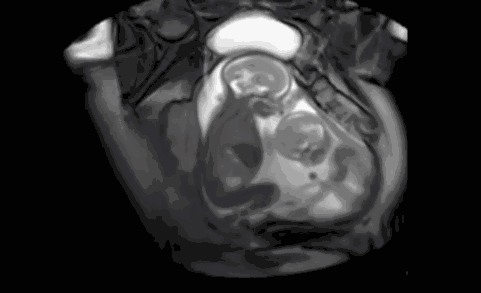

把这个动图看了一遍又一遍

来自弟弟那小小的一脚

可能是他们之间某种独特的交流方式

是在进行拳击比赛

或是争抢狭小的空间

无论哪种方式

这都是生命的奇迹啊